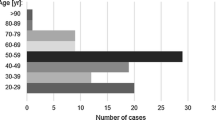

During the preliminary investigation using databases and other approaches, 48 citations were acquired from PubMed, and 6 citations from the Google Scholar database. Following the exclusion of all publications that satisfied at least one exclusion condition, 32 papers were further examined and finally included in the meta-analysis. Table 1 lists each included paper. Figure 2 shows the systematized search synthesis.

Based on the k = 18 included studies (overall cases = 4978; typical = 3494), the PP of the AComA typical morphology was estimated as 0.6732 [0.5716; 0.7674]. Approximately 67% of the population is expected to have the AComA typical morphology (Fig. 3). The estimated heterogeneity was statistically significant (P < 0.0001) based on the Q test statistic, and high degree based on the I^2 statistic (I^2 = 98.1%). The results of the subgroup analyses on the effect of the study’s type and the subjects’ geographical region on the estimated prevalence of the typical morphology are summarized in Table 2. The test for subgroup differences with the study’s design (cadaveric, imaging) as a categorical predictor was not statistically significant (P = 0.6107 > 0.05), and thus the study’s design is not a statistically significant moderator of the estimated prevalence of the typical morphology. To evaluate the geographical region as a possible moderator of the estimated prevalence of the typical morphology, the studies were categorized based on the subjects’ continent of origin. The test for subgroup differences was statistically significant (P = 0.0004). Only one study [23] has been included in the American subgroup, and further studies are required to reach the minimum of four studies per subgroup as suggested by Fu et al. [62] for a (categorical) subgroup variable. The estimated heterogeneity is a high degree in both Asia (I^2 = 95.2%) and Europe (I^2 = 98.8%) subgroups. Therefore, further research is required to confirm this correlation. Subsequently, the presence of the small-study effect was evaluated. The funnel plot of the prevalence against the sample size is depicted in Fig. 3. Based on the regression test, asymmetry in the funnel plot was not statistically significant (P = 0.1774 > 0.05) indicating no small-study effect. In addition, based on the Baujat plot and the leave-one-out forest plot (Fig. 4), no influential outlier studies (with a large impact on both the estimated PP and heterogeneity) were detected. In addition, based on the influence diagnostics results (Fig. 4), no study was identified as influential (red-colored in the diagnostics plots).

Based on the k = 18 included studies (overall cases = 4978; atypical = 1484), the PP of the AComA atypical morphology was estimated as 0.3268 [0.2326; 0.4284]. Approximately 33% of the population is expected to have an atypical morphology (Fig. 5). The estimated heterogeneity was statistically significant (P < 0.0001), and high degree (I^2 = 98.1%). The subgroup analysis results on the effect of the study’s type and the subjects’ geographical region on the estimated prevalence of the atypical morphology are in line with the results for the typical morphology and summarized in Table 2. Based on the test for subgroup differences the study’s design is not a statistically significant moderator of the estimated prevalence of the atypical morphology. In addition, as reported for the typical morphology, further studies are required to confirm a possible correlation between the estimated prevalence of the atypical morphology and the geographical region. Based on the regression test for funnel plot asymmetry (Fig. 5), no small-study effect was detected. In addition, based on the Baujat plot and the leave-one-out forest plot (Fig. 6), no influential outlier studies were detected. The influence diagnostics yielded no study as influential (Fig. 6). The PP of each morphological variant was calculated:

The hypoplastic AComA was studied in 12 articles (a total of 2430 arteries). The PP was 8% [3.1; 14.7] (Fig. 7), with significant heterogeneity (I2 = 95%, P < 0.01).

The fused AComA was encountered in 16 papers, analyzing 4187 vessels. The PP was 5.9% [3.6; 8.6] (Fig. 7), with a significant heterogeneity (I2 = 91%, P < 0.01).

The AComA fenestration was identified in 5 papers including 792 vessels. The PP was 5% [0.9; 11.5], (Fig. 7) with a significant heterogeneity (I2 = 86%, P < 0.01).

The absent AComA was extracted by 21 papers, adding up to 5688 arteries. The PP was 4.6% [2.0; 7.9] (Fig. 7), with a significant heterogeneity (I2 = 96%, (P < 0.001).

The AComA of different shapes Nine articles, including 2329 vessels were included. The PP was 4.5% [2.4; 7.3] (Fig. 7). The heterogeneity was most likely significant (I2 = 82%, P < 0.01).

The AComA duplication was identified in 21 papers, summing 5275 vessels. The PP was 4.3% [2.5; 6.4] (Fig. 7) with a significant heterogeneity (I2 = 90%, P < 0.01).

The persistence of a median artery of the corpus callosum (MACC) was identified in 18 papers, summing 5051 arteries. The PP of the MACC persistence was 2.3% [1.5; 3.2] (Fig. 7), with a moderate heterogeneity (I2 = 63%, P < 0.01).

The AComA triplication was found in 11 studies, which analyzed 3297 arteries. The PP was 0.7% [0.2–1.4] (Fig. 7), with moderate heterogeneity (I2 = 66%, P < 0.01).

Despite the AComA’s great morphological variability and its clinical impact, no study summarizes results for every possible variant. The typical AComA had a 67.3% PP (Type 1), and therefore the atypical patterns occurred with 37.2% (Types 2–8). The atypical patterns will be presented with decreasing frequency. Specifically, the commonest variant was estimated as the AComA hypoplasia with an 8% PP (Type 2). Type 3 was considered the artery’s absence, where it is possible to identify two different morphological types. AComA absence with the two ACAs fused (azygos ACA) had a 5.9% PP (Type 3). Whereas AComA absence with the two ACAs coursed in parallel was estimated with a 4.6% PP (Type 5). An artery is considered fenestrated when its arterial lumen splits into two distinct channels that eventually fuse along its course [36]. Sometimes it is mistaken for duplication, which is defined as the occurrence of two distinct arteries with separate origins [36]. The AComA fenestration was estimated with a 5% PP (Type 4). The AComA could be presented in different shapes (V-shaped, Y-shaped, and plexiform). All possible shapes were considered as AComA was differently shaped with a 4.5% PP (Type 6). In addition, other rarer variants could be present. AComA duplication is estimated at a 4.3% PP (Type 7). A branch emanating directly from the AComA can be identified, which represents an embryological remnant. The MACC persistence had a 2.3% PP (Type 8). The AComA can be identified triplicated in 0.7% (Type 9). Hence, the current meta-analysis proposes a simplified classification system of the AComA morphological variability, by using the PP of its variant in decreasing order (Fig. 12). Nevertheless, it is important to mention some significant results from the meta-analysis subgroup analysis. The typical pattern had a statistically significant difference in a geographic region (America: 82%; Europe: 67%; Asia: 58%), however, only one study was included in the American region (minimum four studies per subgroup [62]). The AComA absence had an interesting statistically significant difference between the studies’ methods. The cadaveric studies’ PP was estimated at 2%, while the imaging studies had a PP of 13% (p < 0.0001). This relationship could be attributed to the difficulty in differentiating small arteries (small diameter and length) in imaging studies. Hence, a small AComA could be misdiagnosed as AComA absence. In cases where there is a hemodynamic imbalance between the ACAs on both sides and no flow through the AComA, it will not be visible on neuroimaging. Another significant methodological difference between the studies was identified in AComA duplication. The cadaveric studies had a 6.5% PP, while the imaging studies PP was 0.9% (P < 0.0001). This relationship could be attributed to the difficulty of diagnosing a second AComA that may be quite small in diameter, during an imaging study. Nevertheless, AComA absence, fusion, duplication, and triplication were identified with a statistically significant difference between geographic regions, whereas only one study was included in the American region (minimum of four studies per subgroup [62]).